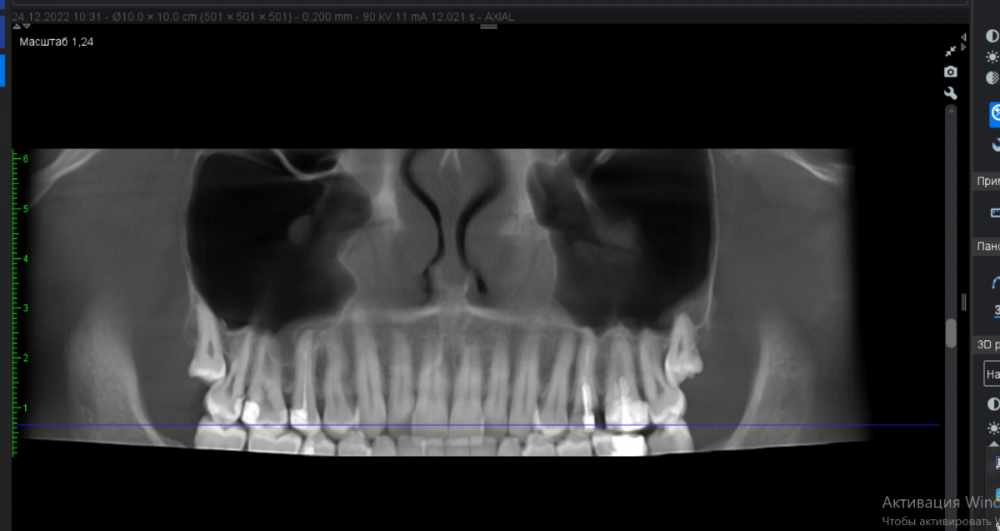

FISSMAN Опубликовано 8 апреля, 2023 Автор Поделиться Опубликовано 8 апреля, 2023 37 минут назад, IvanK сказал: покажите скриншоты Ссылка на комментарий

IvanK Опубликовано 8 апреля, 2023 Поделиться Опубликовано 8 апреля, 2023 пазухи выглядят хорошо 18,28 надо удалять 16,17 лечить 15 - периодонтит - может быть "виновником торжества" (причиной синусита, если обострится) 25, 26 - перелечивание и протезирование 6 часов назад, FISSMAN сказал: КТ сделал в самом начале лечения зубов. если это старый снимок, то имеет смысл делать новый.. 1 Ссылка на комментарий